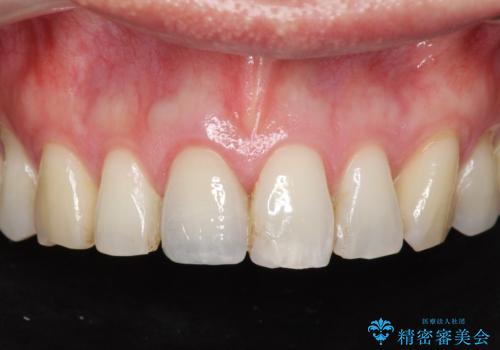

周囲の歯の色調に合わせた、自然なセラミック治療を行うことができましt。

セラミッククラウン製作を行い審美性の改善を計画します。